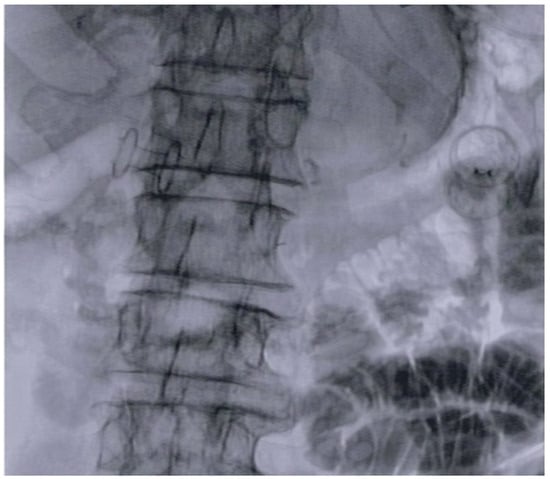

2.1. Procedures